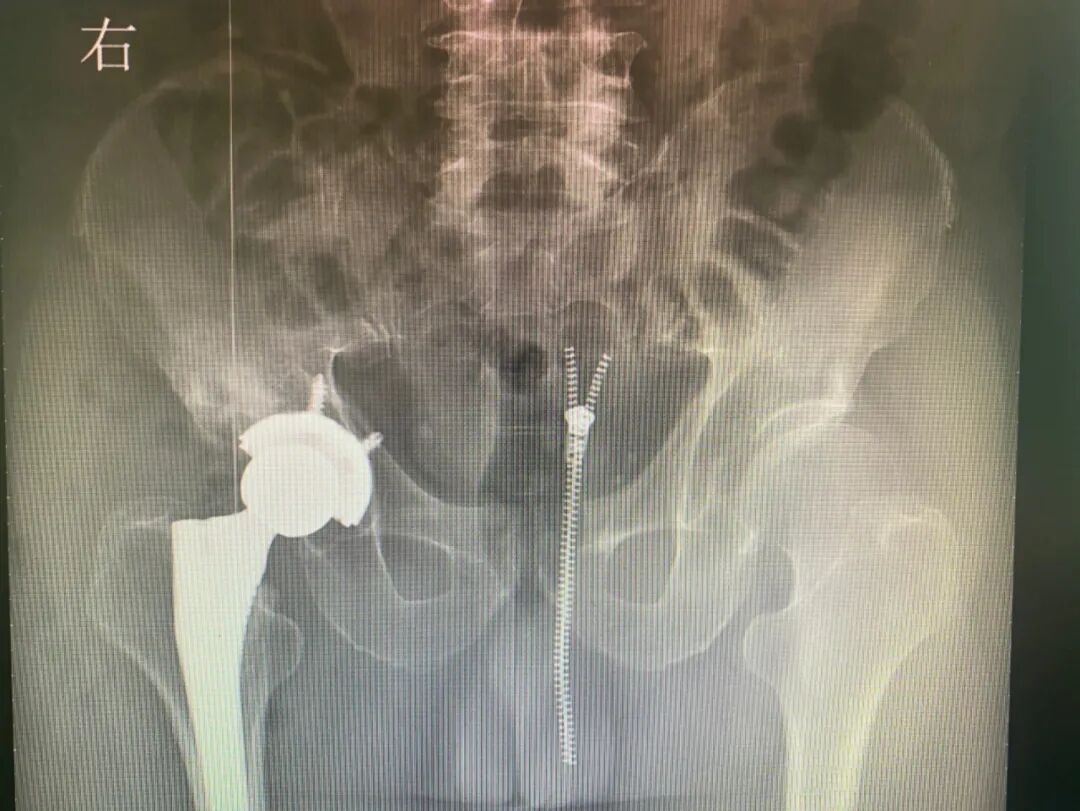

术后

实施医用耗材集中大量采购,是党中央、国务院的重大战略决策部署,是中央深化医疗保障制度改革的重要举措,是增进民生福祉的重要内容。骨科耗材降价,释放政策红利,惠及广大患者。